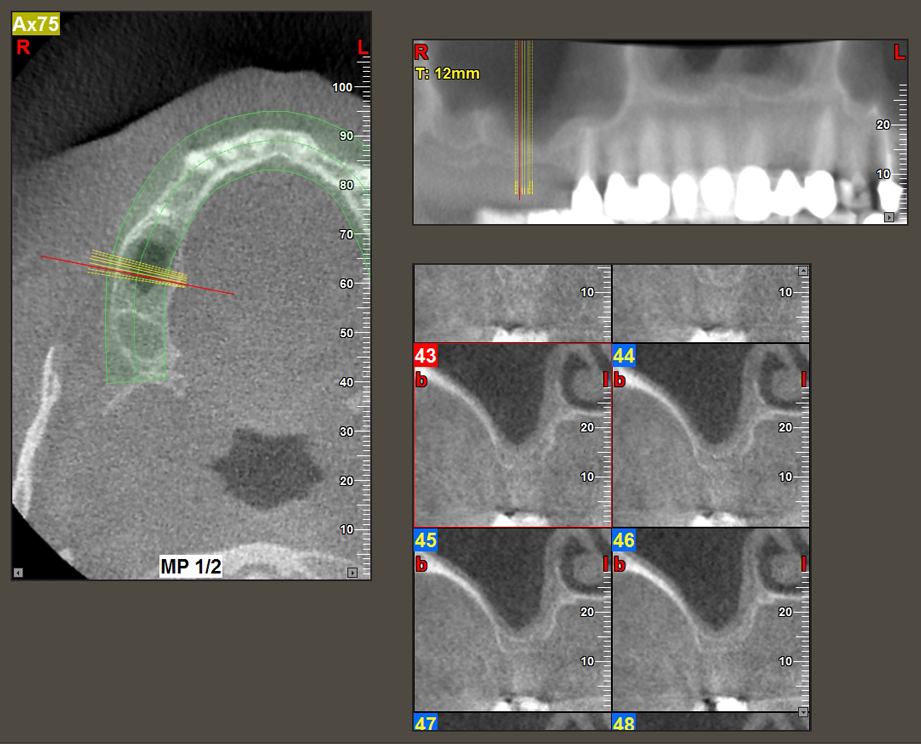

A 49-year-old female patient, a non-smoker and with nothing remarkable in her general medical history, was referred to our oral surgery practice for surgical extraction of tooth 16 and subsequent implantation. After the extraction, the patient experienced mild sinusitis trouble with the resultthat we initially waited six months before carrying out the measure. The residual bone height at the planned implant position measured 3-4 mm (Fig. 1 and 2).

Following an intermediate check (Fig. 4) a further preparation step was performed (Fig. 5). Afterwards, the hydraulic Z35P instrument was used to lift the membrane to the desired position (Fig. 6 and 7). This was followed by further piezosurgical preparation of the implant bed, concluded with a rotary bur and shoulder milling cutter up to the implant diameter of 4.8 mm. Before the implant was inserted, the augmentation material (particle size approx. 0.8-1.6 mm) was introduced underneath the Schneiderian membrane (Fig. 8).